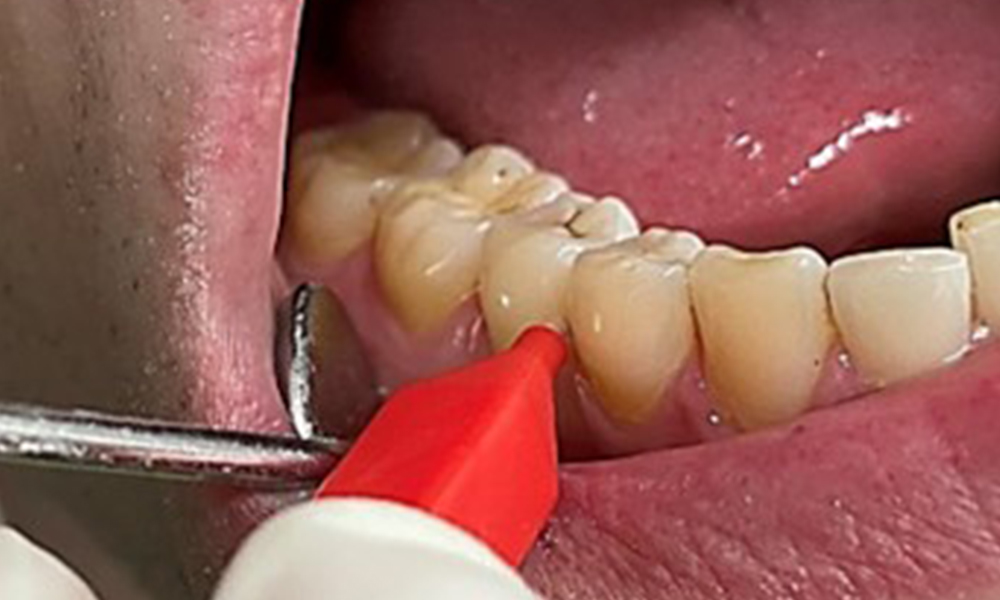

Zugleich ist es notwendig die Interdentalraumbürstchen, welche der

Patient täglich verwendet nach der richtigen Größe zu überprüfen und den Patienten zu bestärken diese konsequent zu benutzen (Abb. 9). Eine

gute Mundhygiene ist unabdingbar, um das Parodontitisrisiko durch das Rauchen zu minimieren.

Anwendung der Interdentalbürstchen in Rg 44/45

Abb. 9: Anwendung der Interdentalbürstchen in Rg 44/45, © Dr. R. Krapf